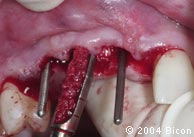

4. | 平行杆就位在经先锋钻预备的牙槽窝内。 |

5. | 插入平行杆,作为邻近牙槽骨预备方向的参考。 |

6. | 插入两根平行杆确认经预备的牙槽窝的方向,并看到暴露出的植骨位点。 |